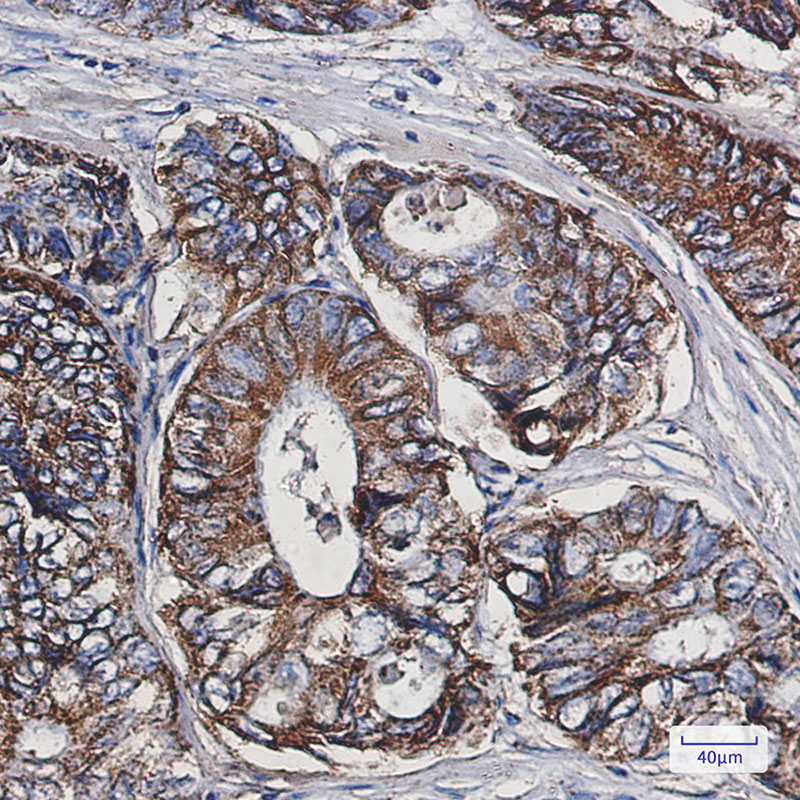

- Immunohistochemistry analysis of paraffin-embedded Human colon cancer using Cpn10 antibody. High-pressure and temperature Sodium Citrate pH 6.0 was used for antigen retrieval.